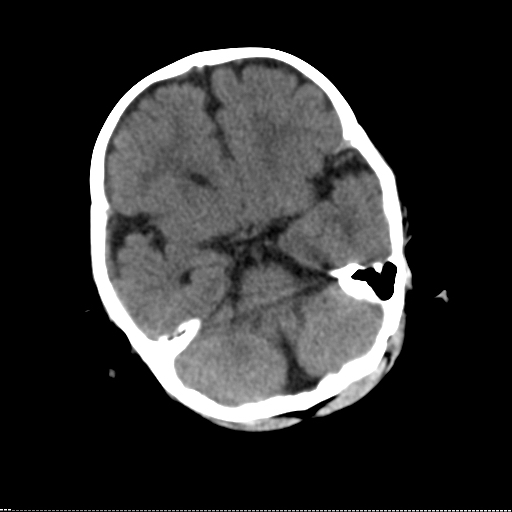

患儿 1岁 不能站立 出牙迟缓。反应尚可,临床怀疑脑发育不良。请各位专家指教。

先天性脑白质发育不良,mri明显

白质区相对少,可疑脑白质发育不良,建议做mri进一步检查。

双侧额叶、颞叶珠网膜下腔、外侧裂池、前纵裂池均增宽,我认为这是较典型的外周性脑积水,大部分患儿到三周岁后能自愈。

应该是外部性脑积水,询问出生时是否有窒息病史,有无颅内感染,外伤等

我也考虑为脑白质发育不良

脑白质发育不良

外周性脑积水